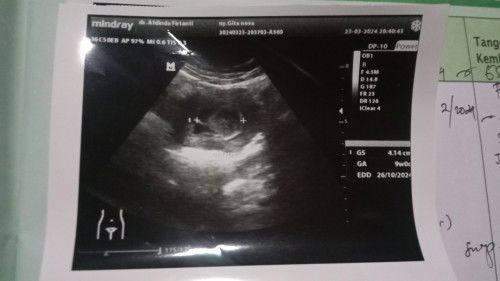

Dsni ada yg punya pengalaman kyk aku gx bun? Aku hamil 23w waktu aku usg pertama di usia 11w di vonis dr gx berkembang cma ada kantong aj tpi keluarga suami sruh yakin dlu alhasil aku nurut , dan di usia 16w aku flek smpe smpet keluar darah seger selama 2minggu lebih dan usg lgi msh kantong aj sma dr di saranin kuret tpi keluarga suami msih ttep kekeuh sruh yakin dlu, dan ini usg aku yg ke3 kta dokter ini bukan janin tpi gumpelan darah dan hrus periksa lebih lanjut di dr obgyn klo hsil ttep sma hrus kuret secepatnya.. Sedih bnget bun aku udh keguguran 2kli dan hrus siap terulang lgi😭 #SeriusTanya